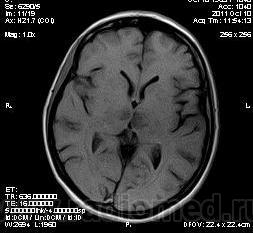

женщина 1963 года рождения. давность заболевания 10 дней.

Билатеральный таламический инфаркт. Либо венозный, либо вследствие закупорки одной из ветвей задней мозговой артерии - ЗМА (вариан развития ЗМА). Но не средней мозговой артерии (СМА). Мне представляеться, что здесь второе... За венозный инфаркт данных не вижу.

MELAS? Чем черт не шутит?

MELAS- по лаколизации очень похоже, но пока нет достоверных данных на него указывающих

Я неприклонен... Инфаркт ЗМА (вероятно, варианта развития левой ЗМА - эмболии, мойа-мойа..).